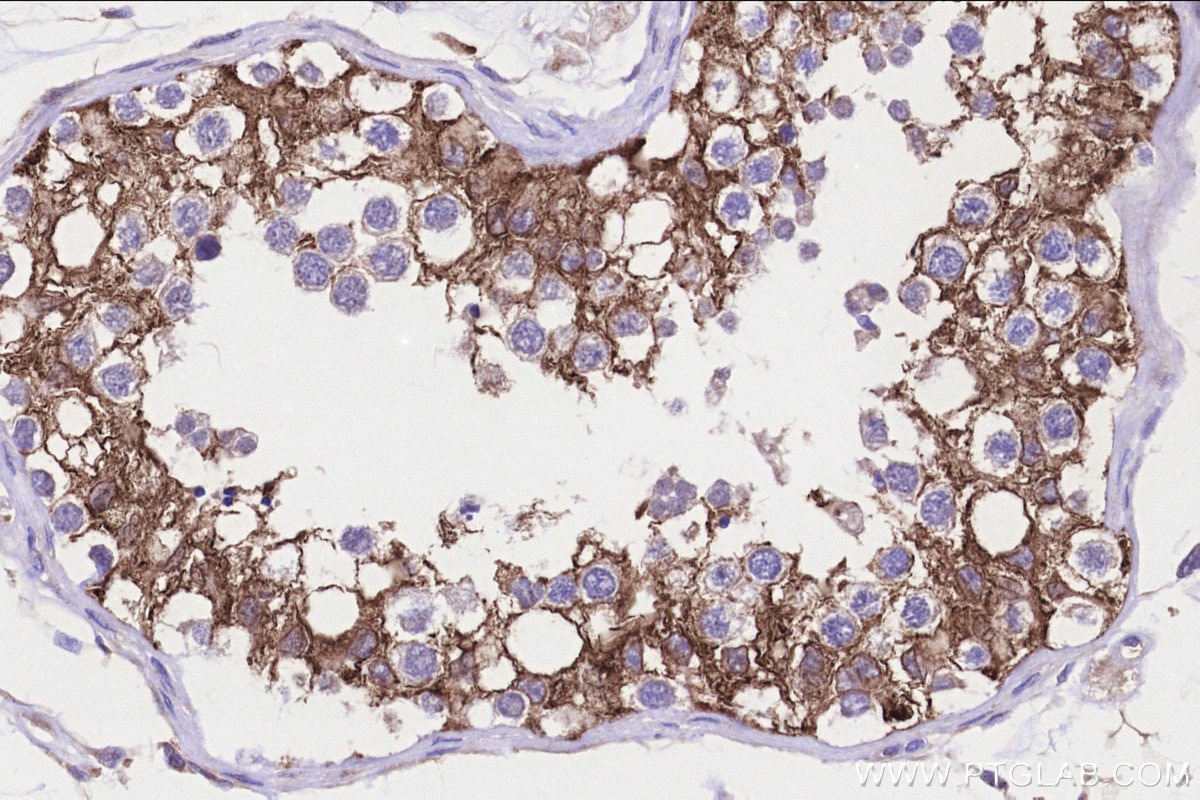

| Positive IHC detected in | human testis tissue Note: suggested antigen retrieval with TE buffer pH 9.0; (*) Alternatively, antigen retrieval may be performed with citrate buffer pH 6.0 |

| Immunohistochemistry (IHC) | IHC : 1:250-1:1000 |

23809-1-AP targets FATE1 in WB, IHC, ELISA applications and shows reactivity with human, mouse samples.

FATE1 ,also named as Fetal and adult testis expressed transcript protein, express predominantly in testis, with some expression in lung, heart, kidney, adrenal gland and whole brain. FATE might represent a novel target gene of SF-1 in testicular differentiation and germ cell development. FATE1 also involves in the regulation of a wide variety of cellular processes ,including the cell cycle, immune responses, signaling cascades and developmental events through target proteins, such as cyclins, cyclin-dependent kinase inhibitors.